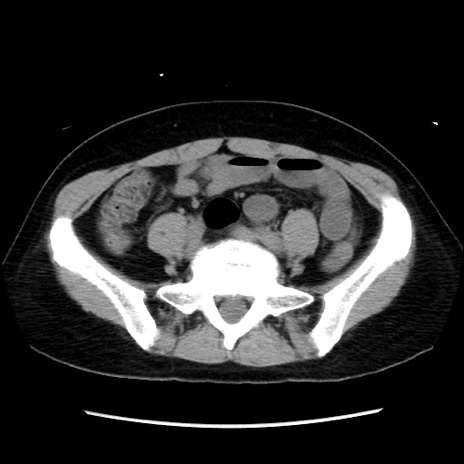

矢状断像

【症例】 50歳代女性

【主訴】 腹痛

【現病歴】前日生レバーを食べた。今朝に排便あり。 昼前に突然発症の腹痛を生じ、当院救急外来を受診した。

【身体所見】 意識清明、腹部:平坦、軟、下腹部やや左を中心に圧痛・反跳痛あり、筋性防御あり

【データ】WBC 7800、CRP 0.07